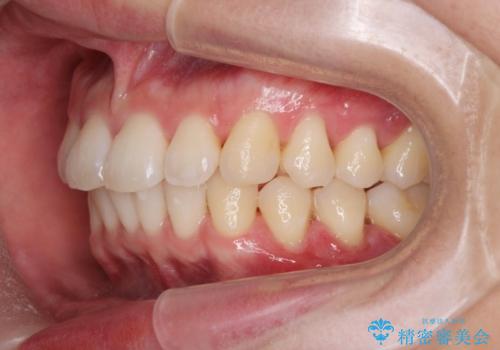

- 20代男性

- ワイヤー

- 10ヶ月

- 取り外しの必要なマウスピース矯正ではなくワイヤー矯正を希望され来院されました。

マウスピース矯正、ワイヤー矯正どちらの方法でも治療は可能ですが、ご要望の通りワイヤー矯正で歯の排列を行っていきます。